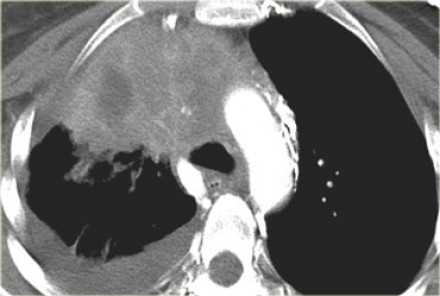

М1а - опухолевые узлы в контрлатеральном легком, опухолевое узелковое поражение плевры, метастатический плевральный или перикардиальный выпот

![]()

Итоговая TNM стадия не-мелкоклеточного рака легкого

Подмножества категорий T, N и M сгруппированы в определенные стадии, так как эти пациенты имеют схожий прогноз [1].

Например, стадия сT1N0 (стадия IA) имеет 5-летнюю выживаемость 77-92%.

С другой стороны рак легкого с любым метастатическим поражением M1c (стадия IVB) имеет 5-летнюю выживаемость равную 0%.